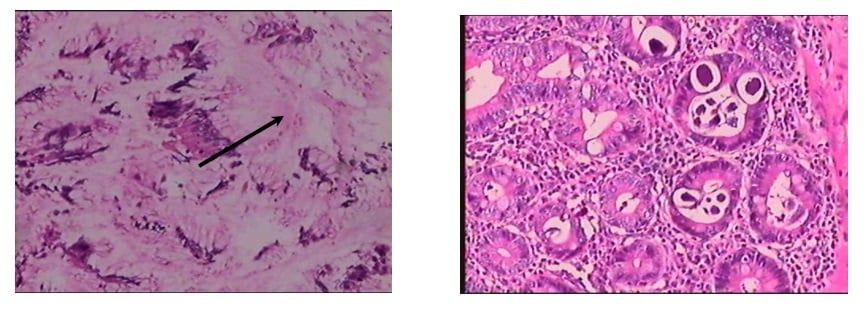

Tuy nhiên, kết quả bất ngờ nằm ở mẫu mô sau khi phẫu thuật. Khi soi dưới kính hiển vi, các bác sĩ Giải phẫu bệnh đã phát hiện ra "thủ phạm" thực sự: Giun lươn đang ký sinh trong niêm mạc ruột non, hoàn toàn không có tế bào ung thư như nghi ngờ ban đầu.

A: Hình ảnh viêm loét dạ dày – B: Hình ảnh giun lươn (Mũi tên) trong ruột non

Nguồn: Khoa Giải phẫu bệnh – Bệnh viện nhân dân 115